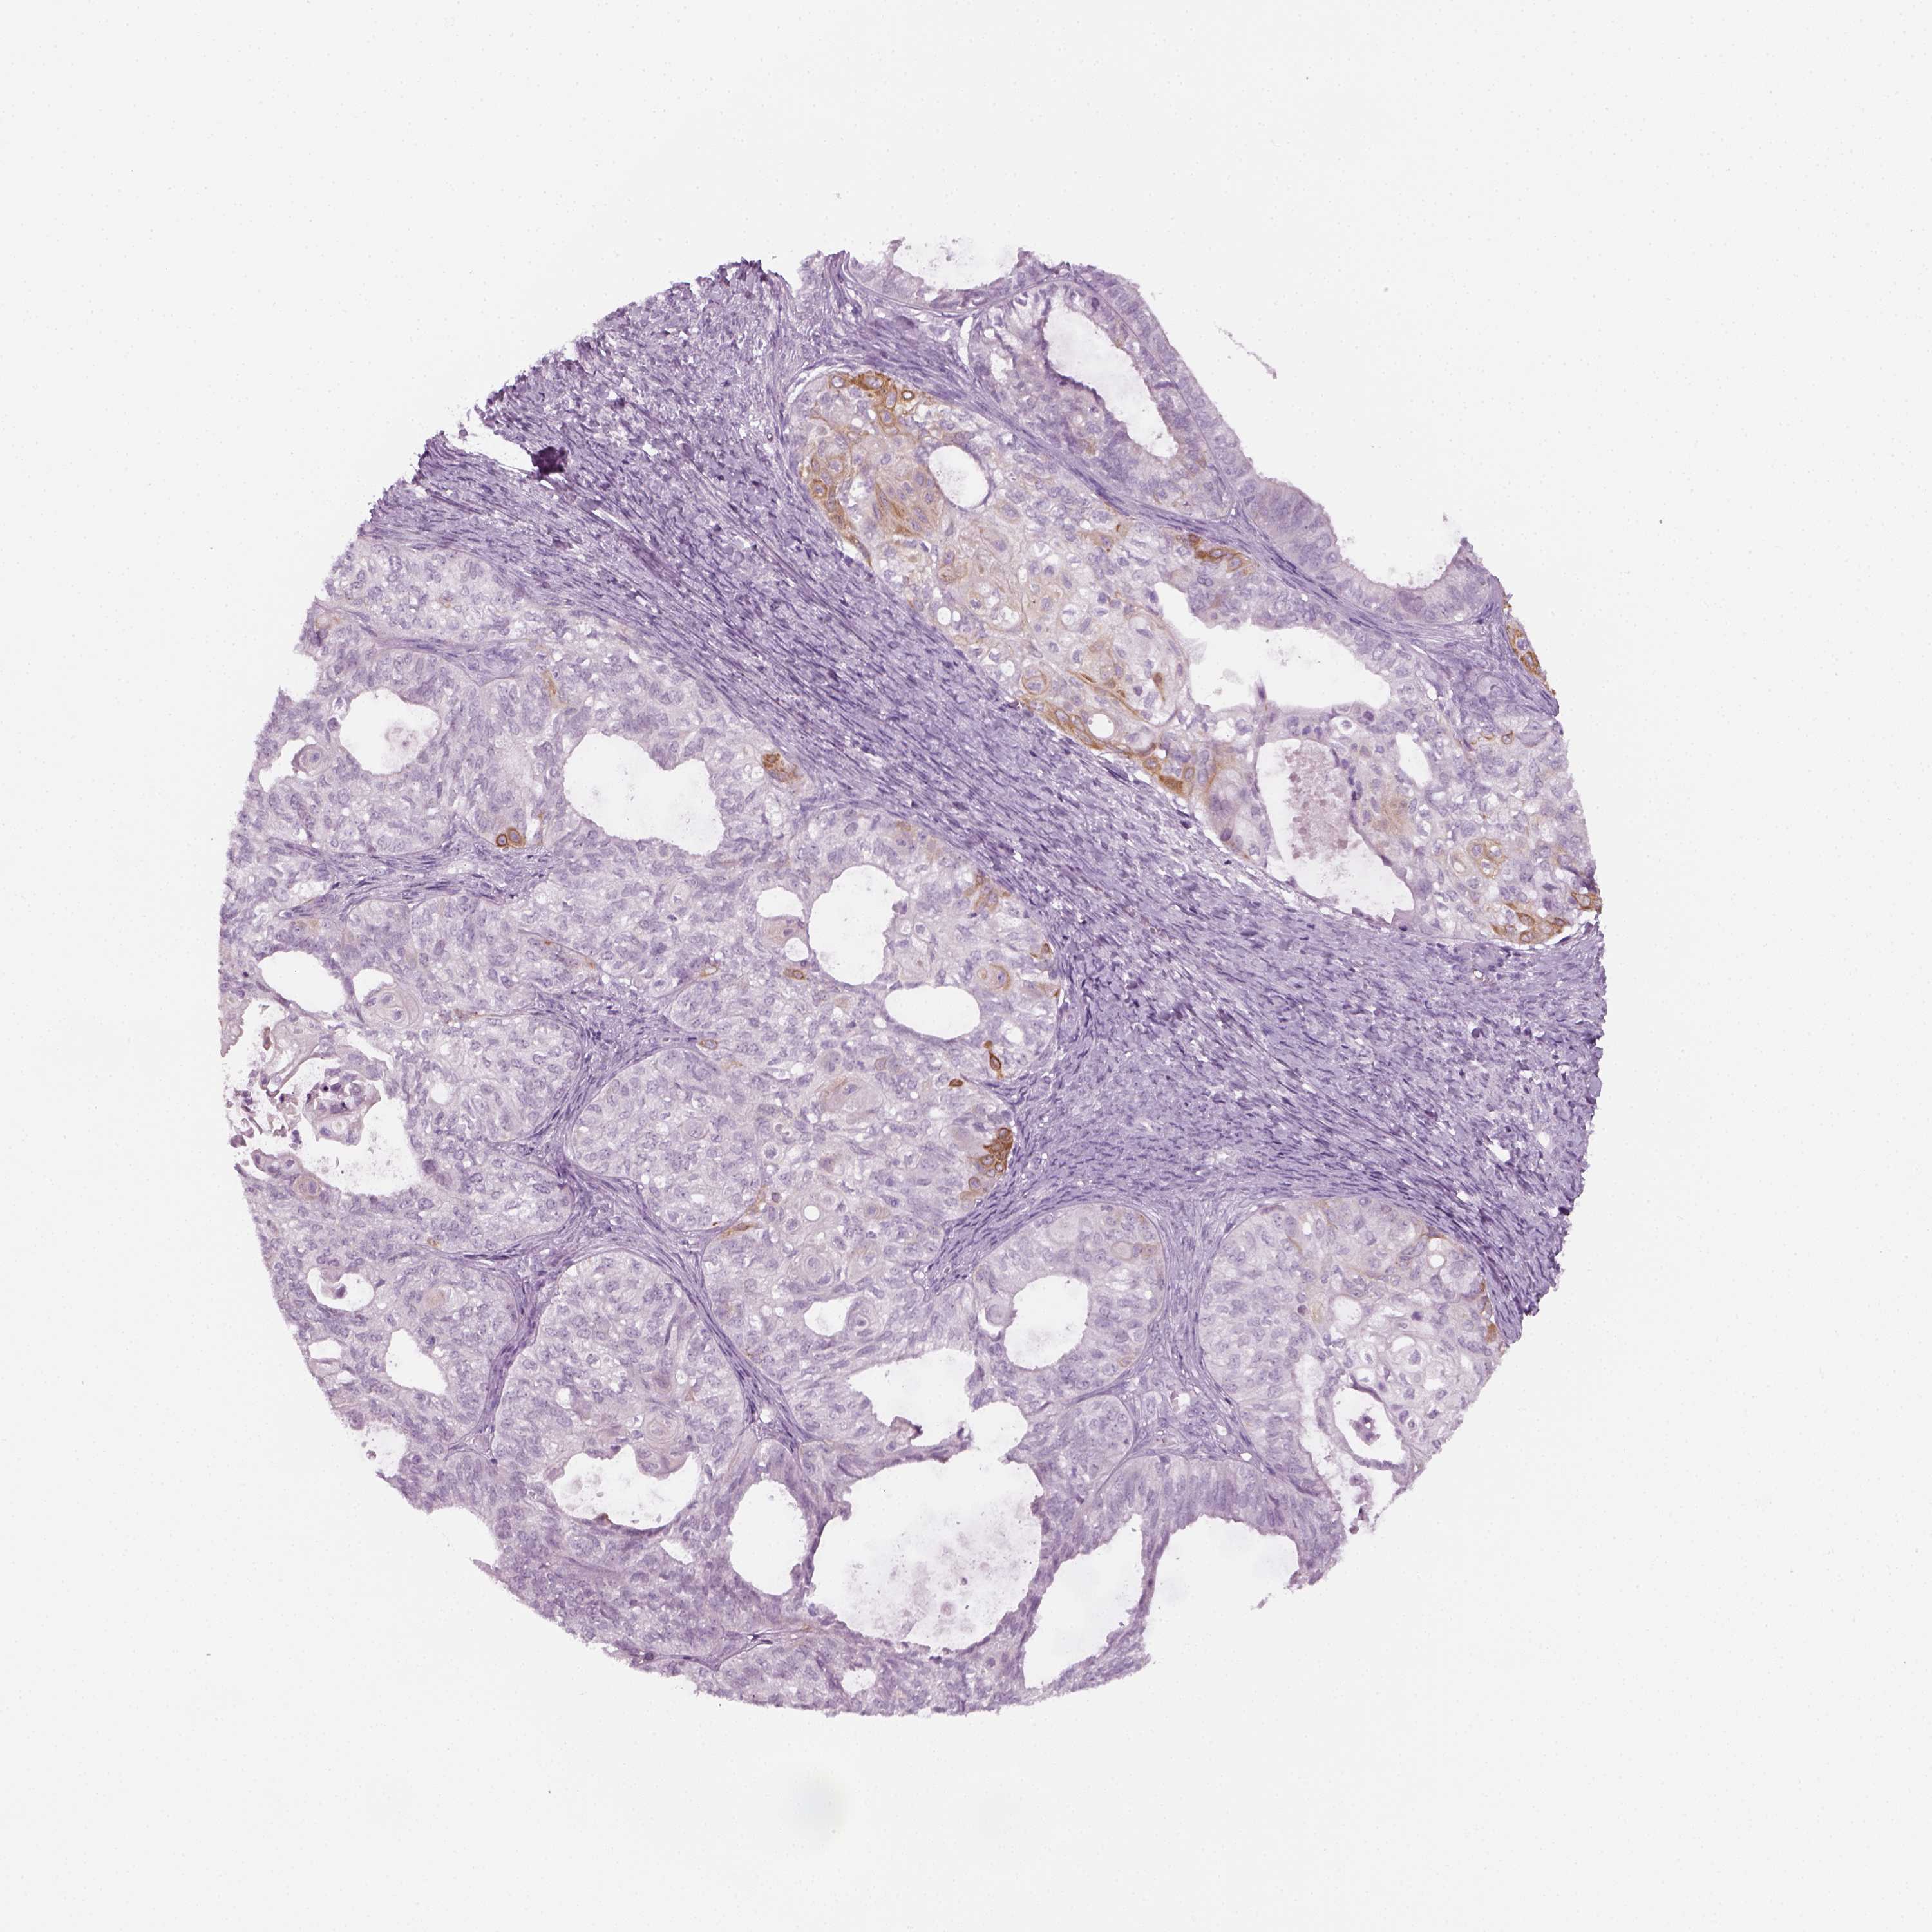

OVARIAN CANCER - Protein expressioni

A mouse-over function shows sample information and annotation data. Click on an image to view it in a full screen mode. Samples can be filtered based on level of antibody staining by selecting one or several of the following categories: high, medium, low and not detected. The assay and annotation is described here.

Note that samples used for immunohistochemistry by the Human Protein Atlas do not correspond to samples in the TCGA dataset.

Antibody stainingi

Antibody staining in the annotated cell types in the current human tissue is reported as not detected, low, medium, or high, based on conventional immunohistochemistry profiling in selected tissues. This score is based on the combination of the staining intensity and fraction of stained cells.

Each image is clickable and will lead to virtual microscopy that enables deeper exploration of all samples and also displays staining intensity scores, fraction scores and subcellular localization as well as patient and tissue information for each sample.

Antibody HPA019367

Antibody HPA076201

Cystadenocarcinoma, serous, NOS

Cystadenocarcinoma, mucinous, NOS

Carcinoma, endometroid